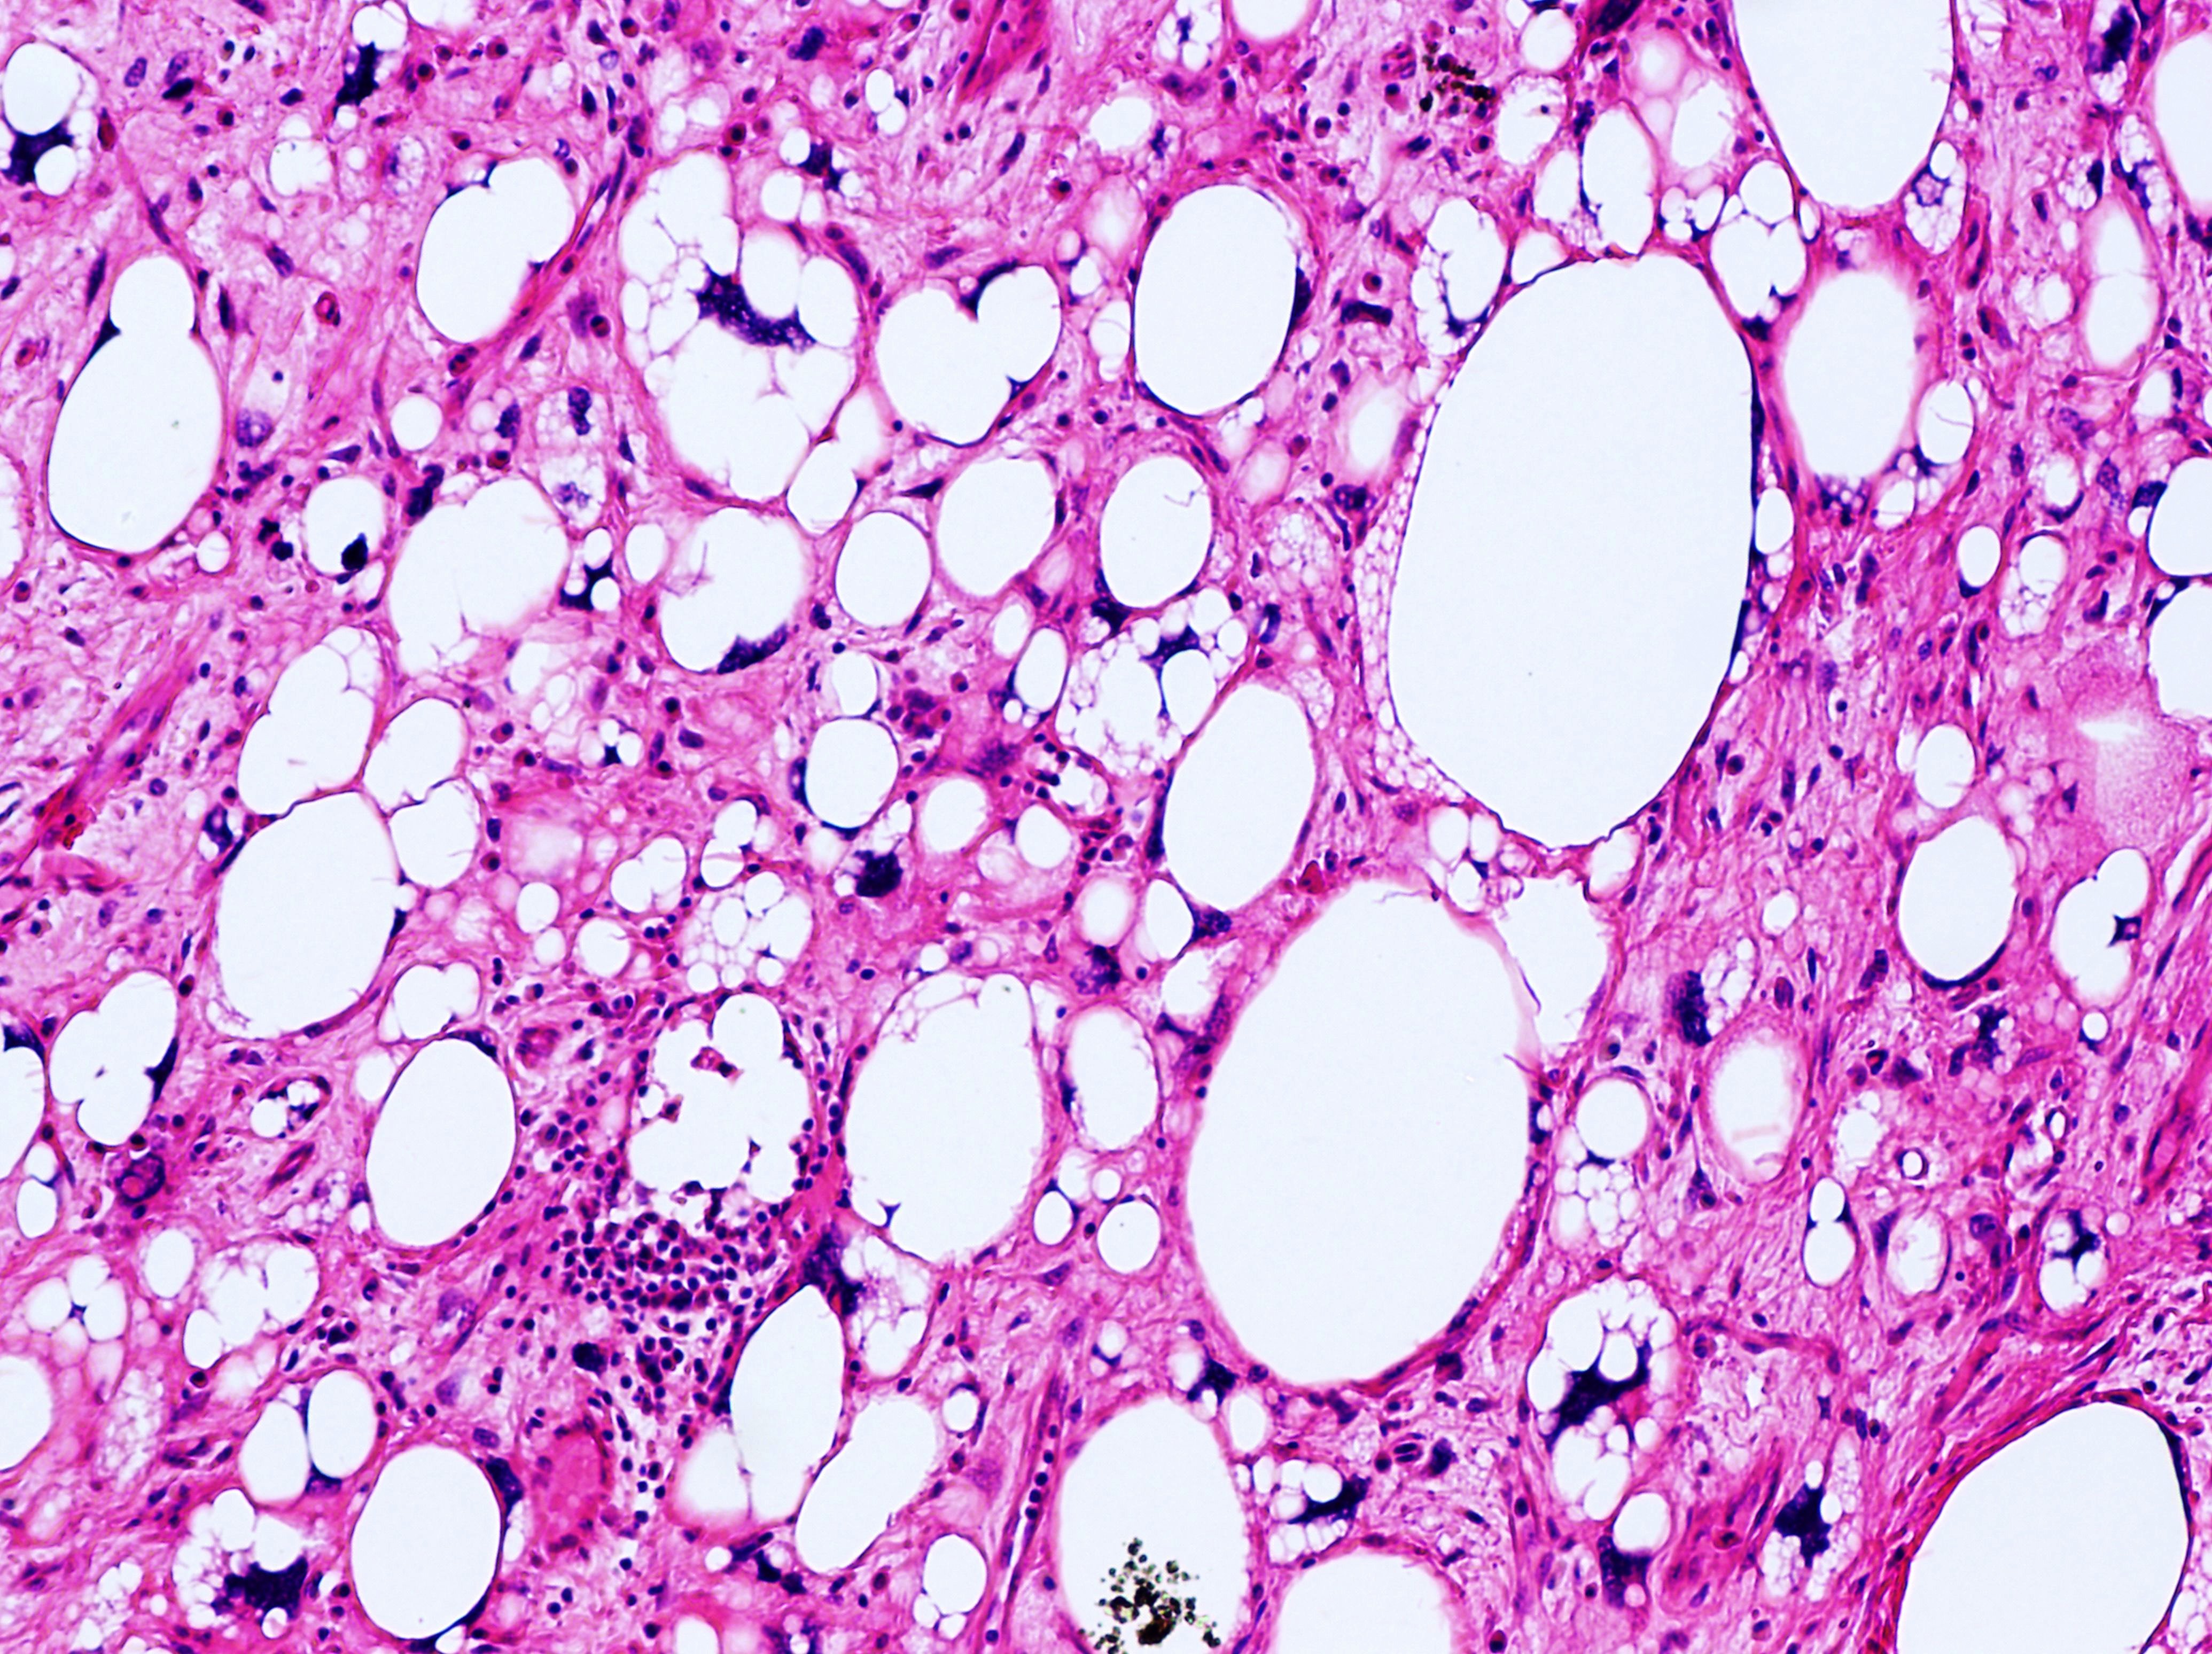

• Anatomical Pathology: This branch of pathology involves the examination of tissues removed from the body during surgery or biopsy to diagnose diseases such as cancer, infections, and inflammatory conditions. Anatomical pathologists analyze tissue samples under a microscope and may use various staining techniques to identify abnormalities.

• Cytopathology: Cytopathology is the study of individual cells obtained from body fluids or tissue samples. Cytopathologists examine cells under a microscope to detect abnormalities indicative of cancer, infection, inflammation, or other diseases. Common cytopathology tests include Pap smears for cervical cancer screening and fine needle aspiration (FNA) biopsies for diagnosing tumors.